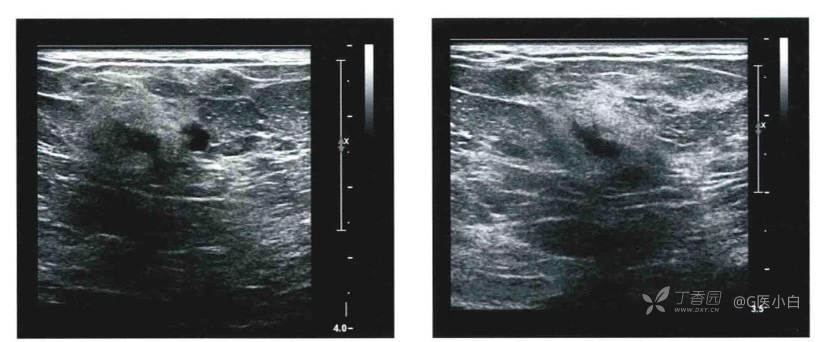

◆完全由微分叶或卵圆形肿块组成的簇状微囊肿。

簇状微囊肿是由一簇大小小于2-3mm的无回声组成的肿块,其内可见厚度<0.5mm的薄层分隔,无实性成分,由于囊肿聚集可能形成微小分叶状边缘,但不应将其边缘描述为模糊。